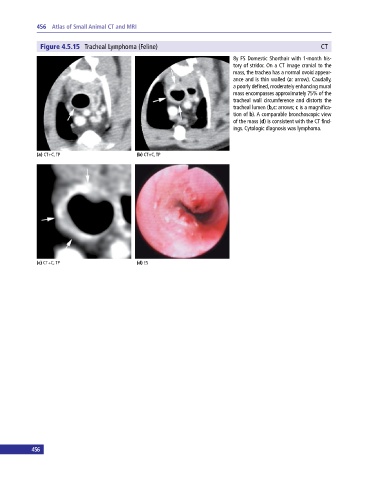

Figure 4.5.15 Tracheal Lymphoma (Feline) CT

8y FS Domestic Shorthair with 1‐month his

tory of stridor. On a CT image cranial to the

mass, the trachea has a normal ovoid appear

ance and is thin walled (a: arrow). Caudally,

a poorly defined, moderately enhancing mural

mass encompasses approximately 75% of the

tracheal wall circumference and distorts the

tracheal lumen (b,c: arrows; c is a magnifica

tion of b). A comparable bronchoscopic view

of the mass (d) is consistent with the CT find

ings. Cytologic diagnosis was lymphoma.

(a) CT+C, TP (b) CT+C, TP

(c) CT+C, TP (d) ES